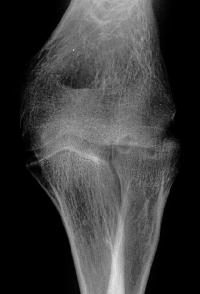

Initial injury: supracondylar fracture in a 9 year old:

Plain films show humeral osteophytes and posttraumatic changes of the capitellum and radial head.